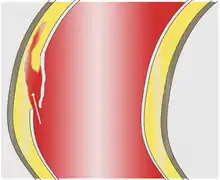

As with all other arteries, the aorta is made up of three layers, the intima, the media, and the adventitia. The intima is in direct contact with the blood inside the vessel, and mainly consists of a layer of endothelial cells on a basement membrane; the media contains connective and muscle tissue, and the vessel is protected on the outside by the adventitia, comprising connective tissue.[25]

In an aortic dissection, blood penetrates the intima and enters the media layer. The high pressure rips the tissue of the media apart along the laminated plane splitting the inner two-thirds and the outer one-third of the media apart.[26] This can propagate along the length of the aorta for a variable distance forward or backward. Dissections that propagate towards the iliac bifurcation (with the flow of blood) are called anterograde dissections and those that propagate towards the aortic root (opposite of the flow of blood) are called retrograde dissections. The initial tear is usually within 100 mm of the aortic valve, so a retrograde dissection can easily compromise the pericardium leading to a hemopericardium. Anterograde dissections may propagate all the way to the iliac bifurcation of the aorta, rupture the aortic wall, or recanalize into the intravascular lumen leading to a double-barrel aorta. The double-barrel aorta relieves the pressure of blood flow and reduces the risk of rupture. Rupture leads to hemorrhaging into a body cavity, and prognosis depends on the area of rupture. Retroperitoneal and pericardial ruptures are both possible.[27]

The initiating event in aortic dissection is a tear in the intimal lining of the aorta. Due to the high pressures in the aorta, blood enters the media at the point of the tear. The force of the blood entering the media causes the tear to extend. It may extend proximally (closer to the heart) or distally (away from the heart) or both. The blood travels through the media, creating a false lumen (the true lumen is the normal conduit of blood in the aorta). Separating the false lumen from the true lumen is a layer of intimal tissue known as the intimal flap.

As blood flows down the false lumen, it may cause secondary tears in the intima. Through these secondary tears, the blood can re-enter the true lumen.